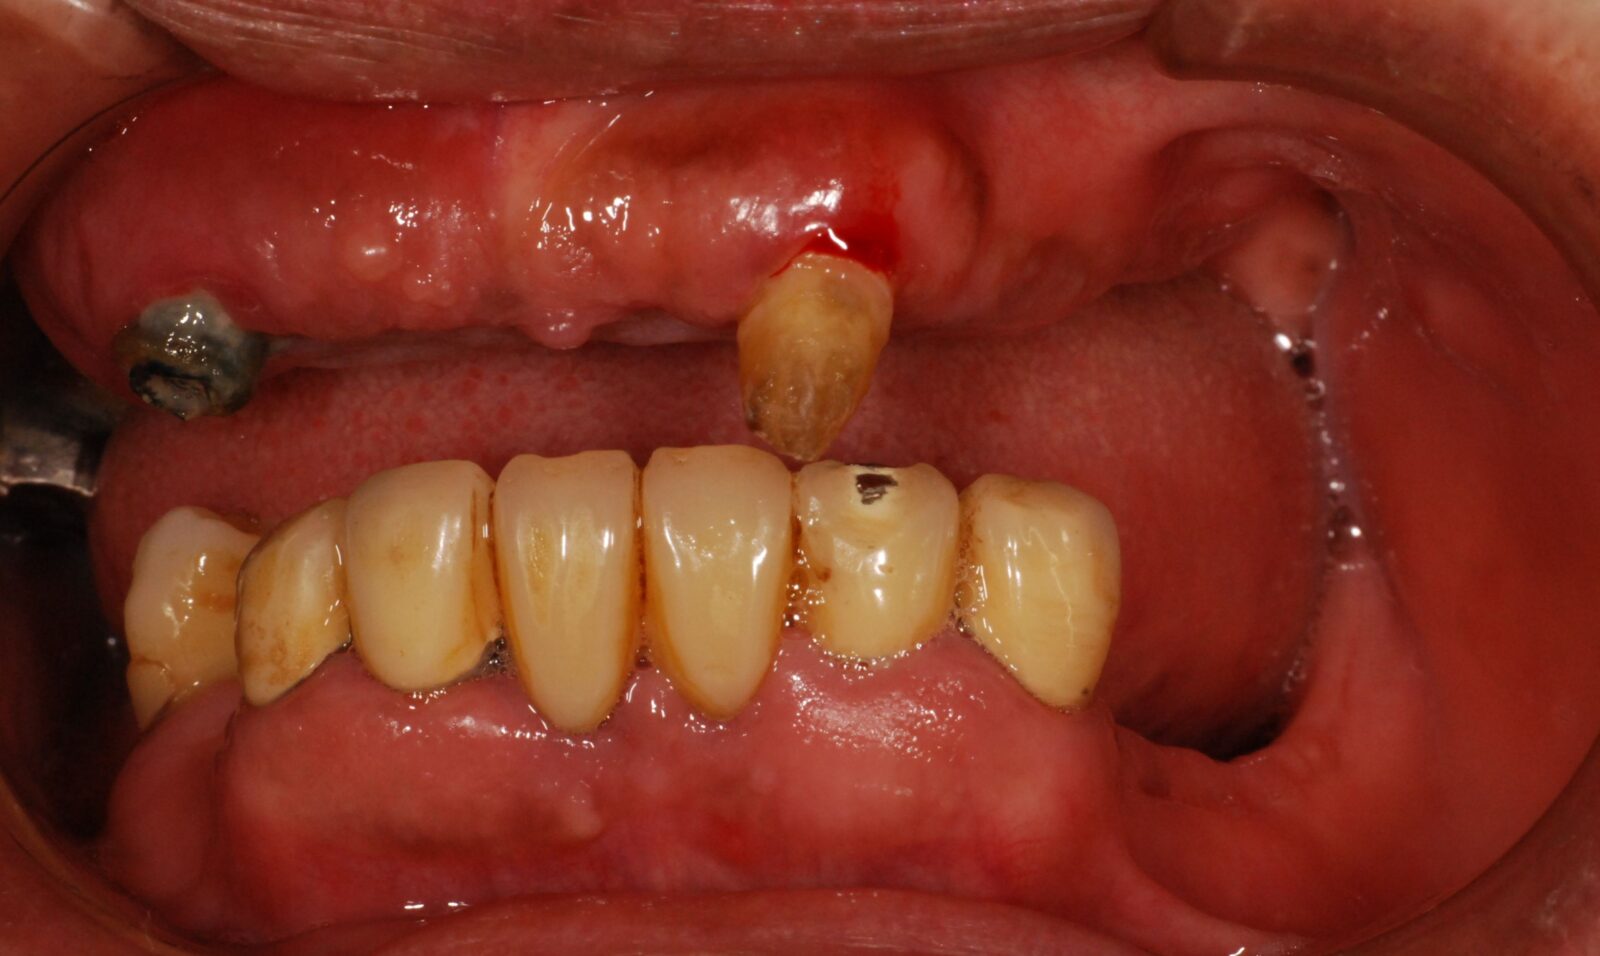

次の写真は、当院で製作した磁性アタッチメント義歯の症例です。

上の写真が、初診時のお口の状態です。

上顎には1本しか歯が残っていませんでしたが、その部分に磁石を取り付けました。総入れ歯にも磁石を取り付け、磁力で入れ歯を固定させました。

下顎にも歯が入っていますが、こちらはインプラント治療で対応しました。